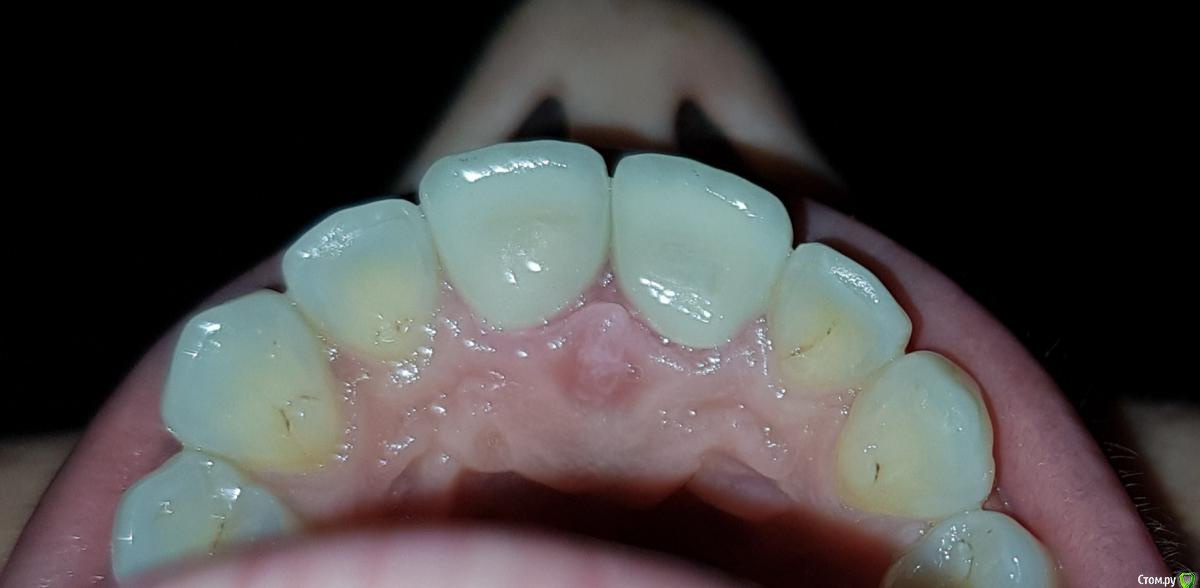

esmeron79 Опубликовано 24 декабря, 2018 Поделиться Опубликовано 24 декабря, 2018 Посоветуйте что делать. Сделали 2 передних циркониевых зуба и пришеечная окантовка оголилась. Почему шейки оголились? Когда врач мерила колпачки, они какие-то оказались большие, но виду не подала. Техник сделал на то что есть. Сосочки воспалены, сзади вообще мешается центральный, набух. Пошла к другому врачу, много счистил цемента, "сосочки" как будто сели, но центральный сзади опять набухает и передние шейки все таки оголены. От чего это могло пройзойти, может большие зубы слишком? Ссылка на комментарий